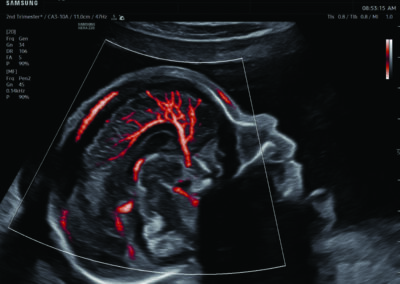

Procedural Services

Comprehensive, advanced and expert MFM care for high-risk pregnancies